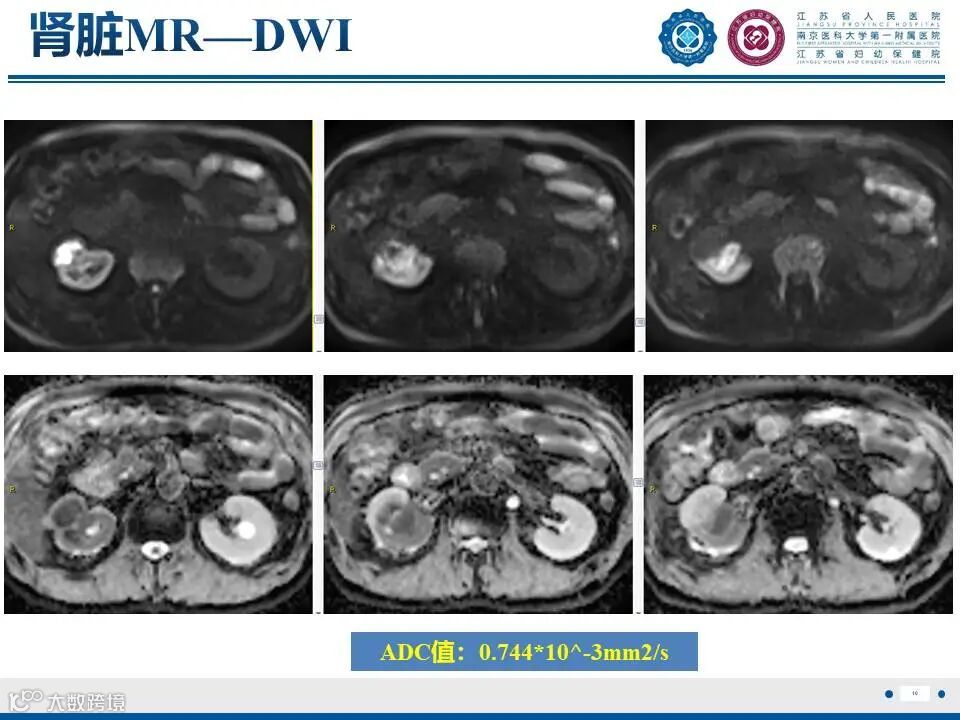

肾实质肾盂尿路上皮癌——水泄不通 II

肾实质肾盂尿路上皮癌——水泄不通 II 鼎湖影像